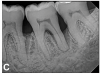

(7.) Progressive improvement in bone quality, quantity, and morphology during each time period, especially in the furcation area of tooth No. 18, which shows a noticeable narrowing of the width of the bony defects, slight apical resorption of the distal root of tooth No. 18, and the encasing of residual cementum on the distal root of No. 19 by new bone formation. Periapical radiographs were taken of teeth Nos. 17, 18, and 19 on June 25, 2016, January 28, 2017, August 23, 2019, and September 4, 2020, respectively, the final of which was taken after almost 5 years post-initial scaling and root planing and alternating supportive periodontal maintenance.

Figure 7

(8.) Progressive improvement in bone quality, quantity, and morphology during each time period, especially in the furcation area of tooth No. 18, which shows a noticeable narrowing of the width of the bony defects, slight apical resorption of the distal root of tooth No. 18, and the encasing of residual cementum on the distal root of No. 19 by new bone formation. Periapical radiographs were taken of teeth Nos. 17, 18, and 19 on June 25, 2016, January 28, 2017, August 23, 2019, and September 4, 2020, respectively, the final of which was taken after almost 5 years post-initial scaling and root planing and alternating supportive periodontal maintenance.

Figure 8

(9.) Progressive improvement in bone quality, quantity, and morphology during each time period, especially in the furcation area of tooth No. 18, which shows a noticeable narrowing of the width of the bony defects, slight apical resorption of the distal root of tooth No. 18, and the encasing of residual cementum on the distal root of No. 19 by new bone formation. Periapical radiographs were taken of teeth Nos. 17, 18, and 19 on June 25, 2016, January 28, 2017, August 23, 2019, and September 4, 2020, respectively, the final of which was taken after almost 5 years post-initial scaling and root planing and alternating supportive periodontal maintenance.

Figure 9

(10.) Progressive improvement in bone quality, quantity, and morphology during each time period, especially in the furcation area of tooth No. 18, which shows a noticeable narrowing of the width of the bony defects, slight apical resorption of the distal root of tooth No. 18, and the encasing of residual cementum on the distal root of No. 19 by new bone formation. Periapical radiographs were taken of teeth Nos. 17, 18, and 19 on June 25, 2016, January 28, 2017, August 23, 2019, and September 4, 2020, respectively, the final of which was taken after almost 5 years post-initial scaling and root planing and alternating supportive periodontal maintenance.

Figure 10

The patient's periodontal disease improved with initial nonsurgical periodontal therapy that involved scaling and root planing. This initial treatment was followed by only SPT every 3 months. Despite treatment, residual deep periodontal probing depths remained, so a decision was made to maximize improvements with nonsurgical therapy and to reassess as needed to determine whether surgical intervention was appropriate. After almost 5 years of SPT and good patient compliance with plaque control and supportive care, the periodontium was stable. Because of the resulting bone formation and improvements in clinical attachment levels (Figure 7 through Figure 13), it was determined that periodontal surgical intervention was not necessary.

In the case report presented, treatment with nonsurgical therapy for 5 years effectively halted destruction and led to bone regeneration and improved clinical attachment levels. Although the primary etiology of periodontal disease is well documented, secondary etiologic and contributing factors are numerous.16 After initial therapy in the current case, there was radiographic evidence of a hypercementosis-like lesion on the distal root of tooth No. 19 (Figure 7 through Figure 10). Hypercementosis is a nidus for plaque accumulation leading to disease progression; however, the presence of this lesion did not explain the disease severity observed for tooth No. 18. Chronic periodontitis is the most widespread form of periodontal disease, and nonsurgical periodontal therapy is the most common type of therapy.17 Scaling and root planning is the gold standard for periodontal treatment. When performed meticulously, they result in improvement of clinical parameters through changes related to tissue shrinkage, long junctional epithelium, new attachment, and in rare circumstances, regeneration.18 The use of nonsurgical periodontal therapy for treatment of periodontal disease requires that the timing for re-evaluation is customized for each patient. Because individuals heal at different rates, the overall medical condition, nutritional intake, environmental and social risks factors, local factors, and colonization of pathogenic bacteria of patients should be considered.7,8 Some patients cannot afford, or choose not to pursue, surgical periodontal therapy. For these patients, clinicians should delay surgical decisions until periodontal risk factors are addressed and nonsurgical efforts are exhausted.